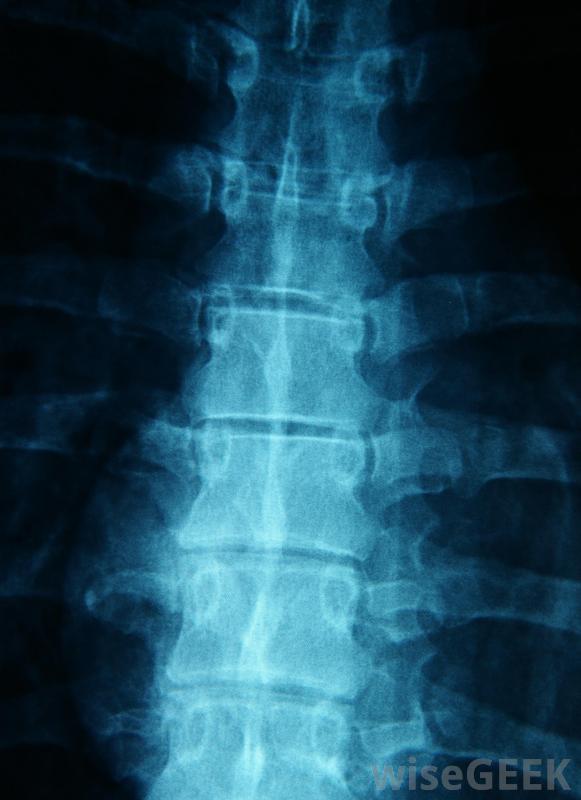

层间硬膜外注射的工作原理是进入包裹脊神经的硬脑膜周围区域。所有从脊椎进入手臂、腿部和胸部的神经都经过这个区域。注射过程中,针头直接插入薄膜,将类固醇输送到狭小的空间。

在层间硬膜外注射过程中,静脉注射首先输送麻醉剂,这样身体就可以放松注射。病人被放在他或她的胃部的x光台上,注射区域周围的皮肤被消毒。此时,另一种麻醉剂被注射到注射区进一步放松神经末梢,使其疼痛。一种称为透视的x光片可以让医生将针头精确地引导到脊椎的正确位置。接下来,进行两次注射:一种是一种特殊的染料,可以确保类固醇的靶向正确的区域,另一种是类固醇本身,它与另一种麻醉剂联合使用,以保持患者的舒适。

椎管间硬膜外注射通常用于治疗脊柱三个部位之一的炎症。在颈段硬膜外注射中,类固醇可以减轻颈、肩和臂的疼痛。腰段硬膜外注射会影响下背部、臀部和臀部的疼痛,以及腿部的不适感药物可以治疗上背部、肋骨的炎症,在某些情况下,腹部。大约50%的患者报告在接受层间硬膜外注射后,患处疼痛明显减轻。